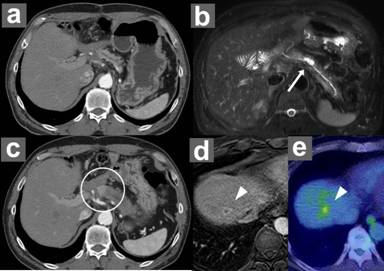

Thereafter, the patient was surveyed using alternate CT and MRCP at 6-month intervals to check for possible occurrence of distinct PDAC and morphological changes of the residual IPMN in the remnant pancreas according to our postoperative surveillance protocol after resection of IPMN [6]. Postoperative imaging studies, such as CT at 6 months and MRCP at 12 months postoperatively, showed no morphological changes of the residual branch duct IPMN and no evidence of a new lesion in the remnant pancreas (Figure 4ab). Notably, although the serum CEA level decreased to 2.4 ng/mL immediately after the operation, it increased to 4.4 ng/mL 12 months after the operation. At 18 months after the operation (i.e., 6 months after the latest MRCP), the serum CEA and CA 19-9 levels increased to 6.5 ng/mL and 55.4 IU/mL, respectively; the hemoglobin A1c level also increased to 7.0% (reference range: 4.3-5.8%). Enhanced CT 18 months after the operation showed a 20-mm diameter solid mass with delayed enhancement in the remnant pancreas (Figure 4c). EUS-guided fine needle aspiration cytology revealed adenocarcinoma. In addition, MRI and positron emission tomography revealed a solitary liver metastasis in the right hepatic lobe (Figure 4de). The patient was diagnosed with PDAC with liver metastasis and subsequently underwent chemotherapy using gemcitabine; however, he died 9 months after the diagnosis of PDAC.

Figure 4. Postoperative imaging studies. a. Enhanced CT 6 months after the operation shows no evidence of recurrence. b. MRCP 12 months after the operation also shows no morphological changes of the residual branch duct IPMN (white arrow) and no evidence of a new lesion in the remnant pancreas. c. Enhanced CT 18 months after the operation shows a solid mass with delayed enhancement in the remnant pancreas (white circle). d. Enhanced MRI reveals a ring-enhanced solid mass in the right lobe of the liver, indicating a liver metastasis (arrowhead). e. Positron emission tomography also reveals a solitary liver metastasis in the right lobe of the liver. |